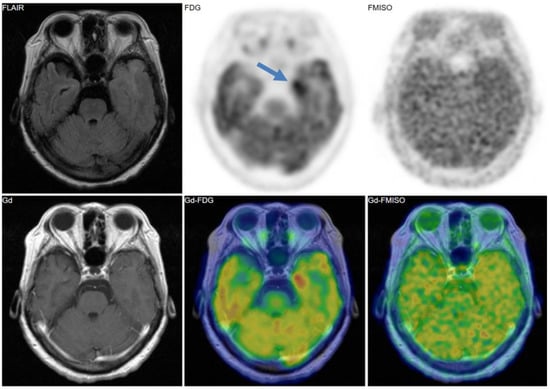

Figure 2. A 69-year-old patient had a tumor in the left temporal lobe. Fluid-attenuated inversion recovery (FLAIR) image showed high intensity, indicating the tumor and the peritumoral edema. Gadolinium enhancement, 18F-fluorodeoxyglucose (FDG) uptake, and FMISO uptake were observed in the same area. The pathological diagnosis was glioblastoma (grade IV).

Figure 2, Figure 3 and Figure 4 show some representative cases of low to high grade gliomas. We demonstrated that FMISO has the potential to distinguish glioblastomas (i.e., grade IV gliomas) from less-malignant gliomas (i.e., grade III or lower grade gliomas) [40]. As mentioned above, the oxygen concentration threshold of FMISO uptake is low. Thus, FMISO PET can differentiate tissues with severe hypoxia from those without. Studies using direct needle electrodes suggested that the hypoxic condition of a glioma depends on its degree of malignancy [41,42,43]. We used FMISO PET and FDG PET for the preoperative examination of 23 patients with gliomas of different World Health Organization (WHO) grades [40]. The PET findings were compared with the patients’ post-operative histological findings by neuropathologists. We observed FMISO uptake in the glioblastomas, but not in the less-malignant gliomas (Table 1). In the WHO definition, glioblastoma presents with necrosis in the tumor, whereas lower-grade gliomas do not develop necrosis [44]. It is thus reasonable that only glioblastomas have severe hypoxia (beyond the FMISO threshold) and therefore take up FMISO. We concluded that FMISO PET may be able to clearly distinguish glioblastomas from lower-grade gliomas.